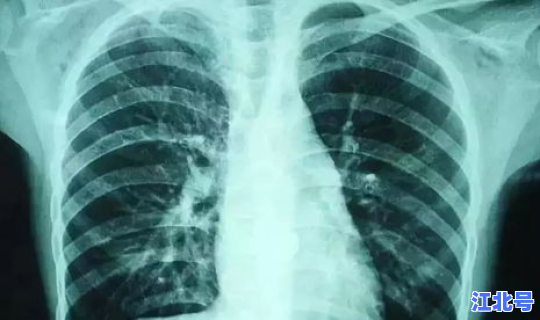

这个病例是怎么回事哈尔滨新冠确诊病例行动轨迹?这个病例发生在黑龙江省哈尔滨市,哈尔滨的某居民因为之前曾经和境外病例有过接触,所以被传染了新冠肺炎 。在这位居民被确诊新冠肺炎之后 ,这位居民已经被隔离治疗。居民本身的症状属于轻症,所以并没有生命危险。这名患者是因为接触境外病例而传染的新冠肺炎 。